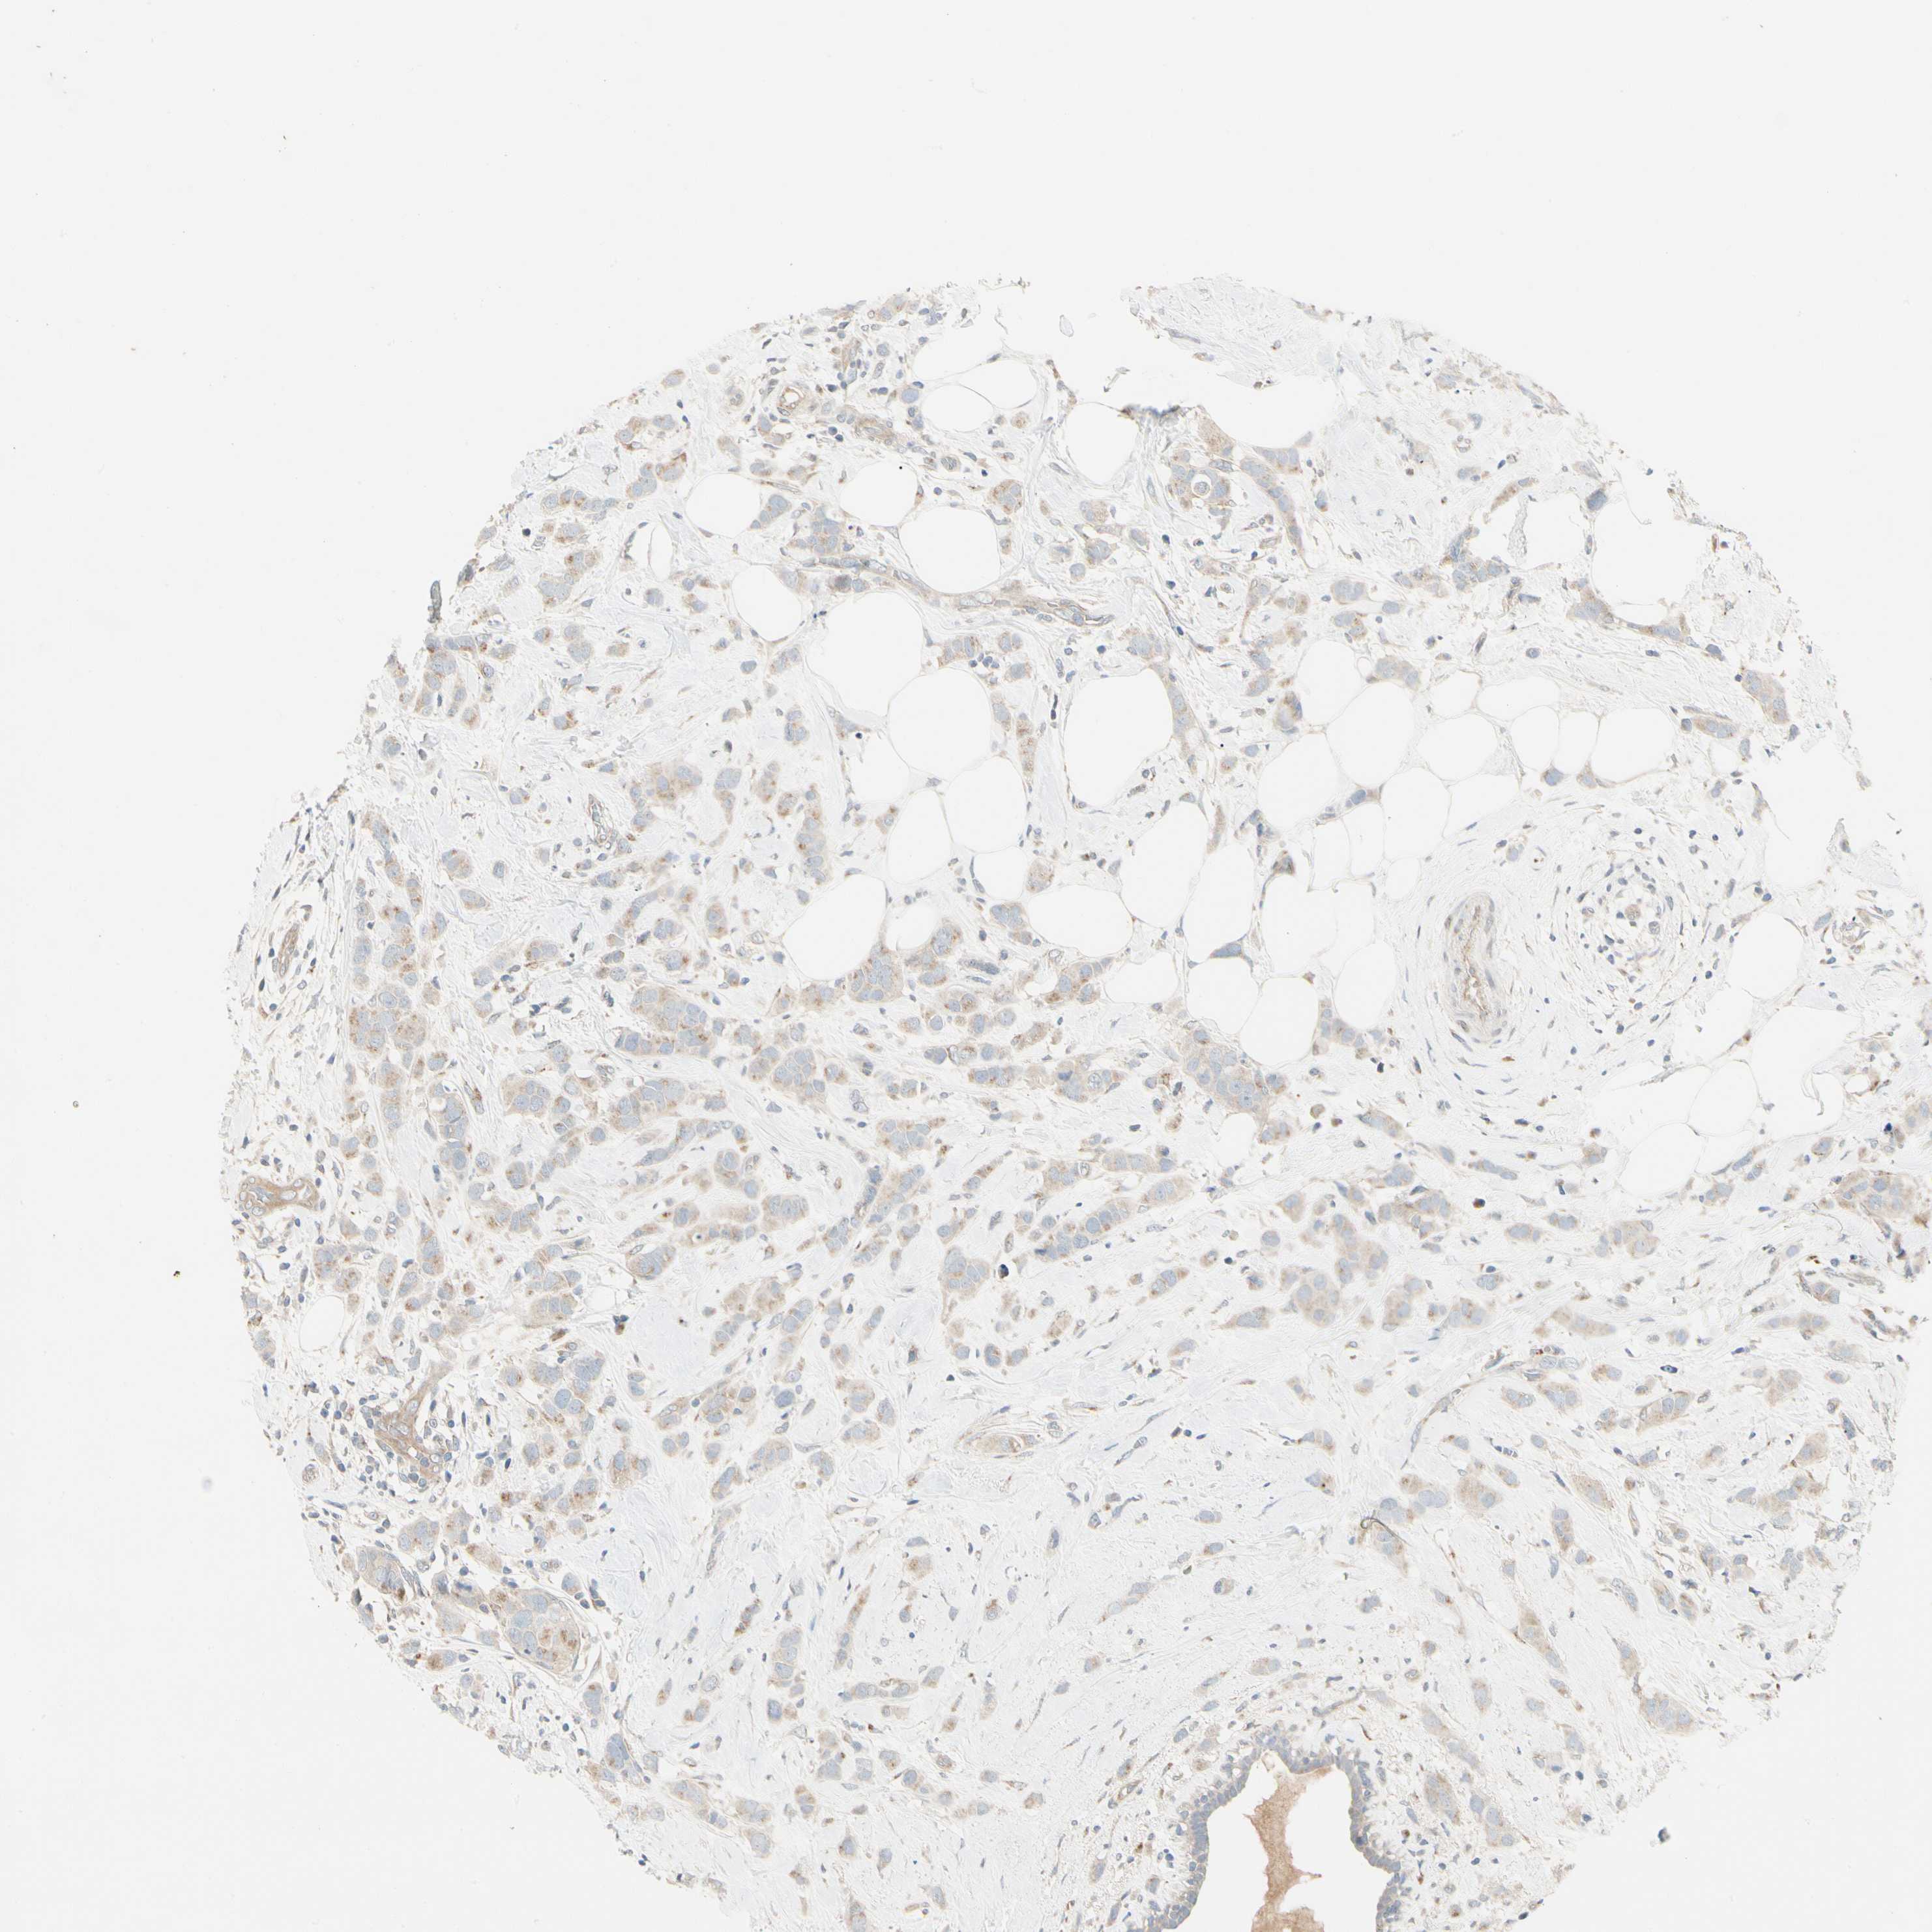

CANCER BREAST CANCER Show tissue menu

BRCA TCGA BRCA VALIDATION PROTEIN EXPRESSION